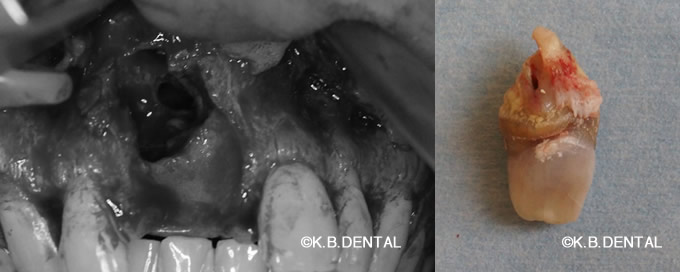

正中過剰埋伏歯(せいちゅうかじょうまいふくし)

正中過剰埋伏歯 症例

正中過剰埋伏歯の症例です。鼻腔底直下にあるので、静脈内鎮静を使い無痛抜歯で対応しました。抜歯が怖い方はご相談下さい。

料金は保険適用で約10,000円の治療費用です。